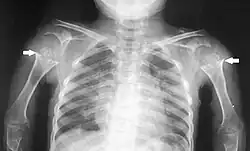

Die Diagnose wird oftmals nicht bei Geburt, sondern erst beim Kleinkind im Alter von zwei bis drei Jahren vermutet. Die Diagnosesicherung erfolgt mithilfe des Röntgenbildes. Kriterien sind:[7][1]

- Ovale bis dreieckige Wirbelkörper, Hypoplasie des Dens, typischerweise mit Instabilität im Atlantoaxialgelenk

- kolbig aufgetriebene Metaphysen

- verzögerte Entwicklung der Epiphysen mit fragmentierten Ossifikationszentren an Hüft- und Kniegelenk mit Ausbildung einer Coxa vara.